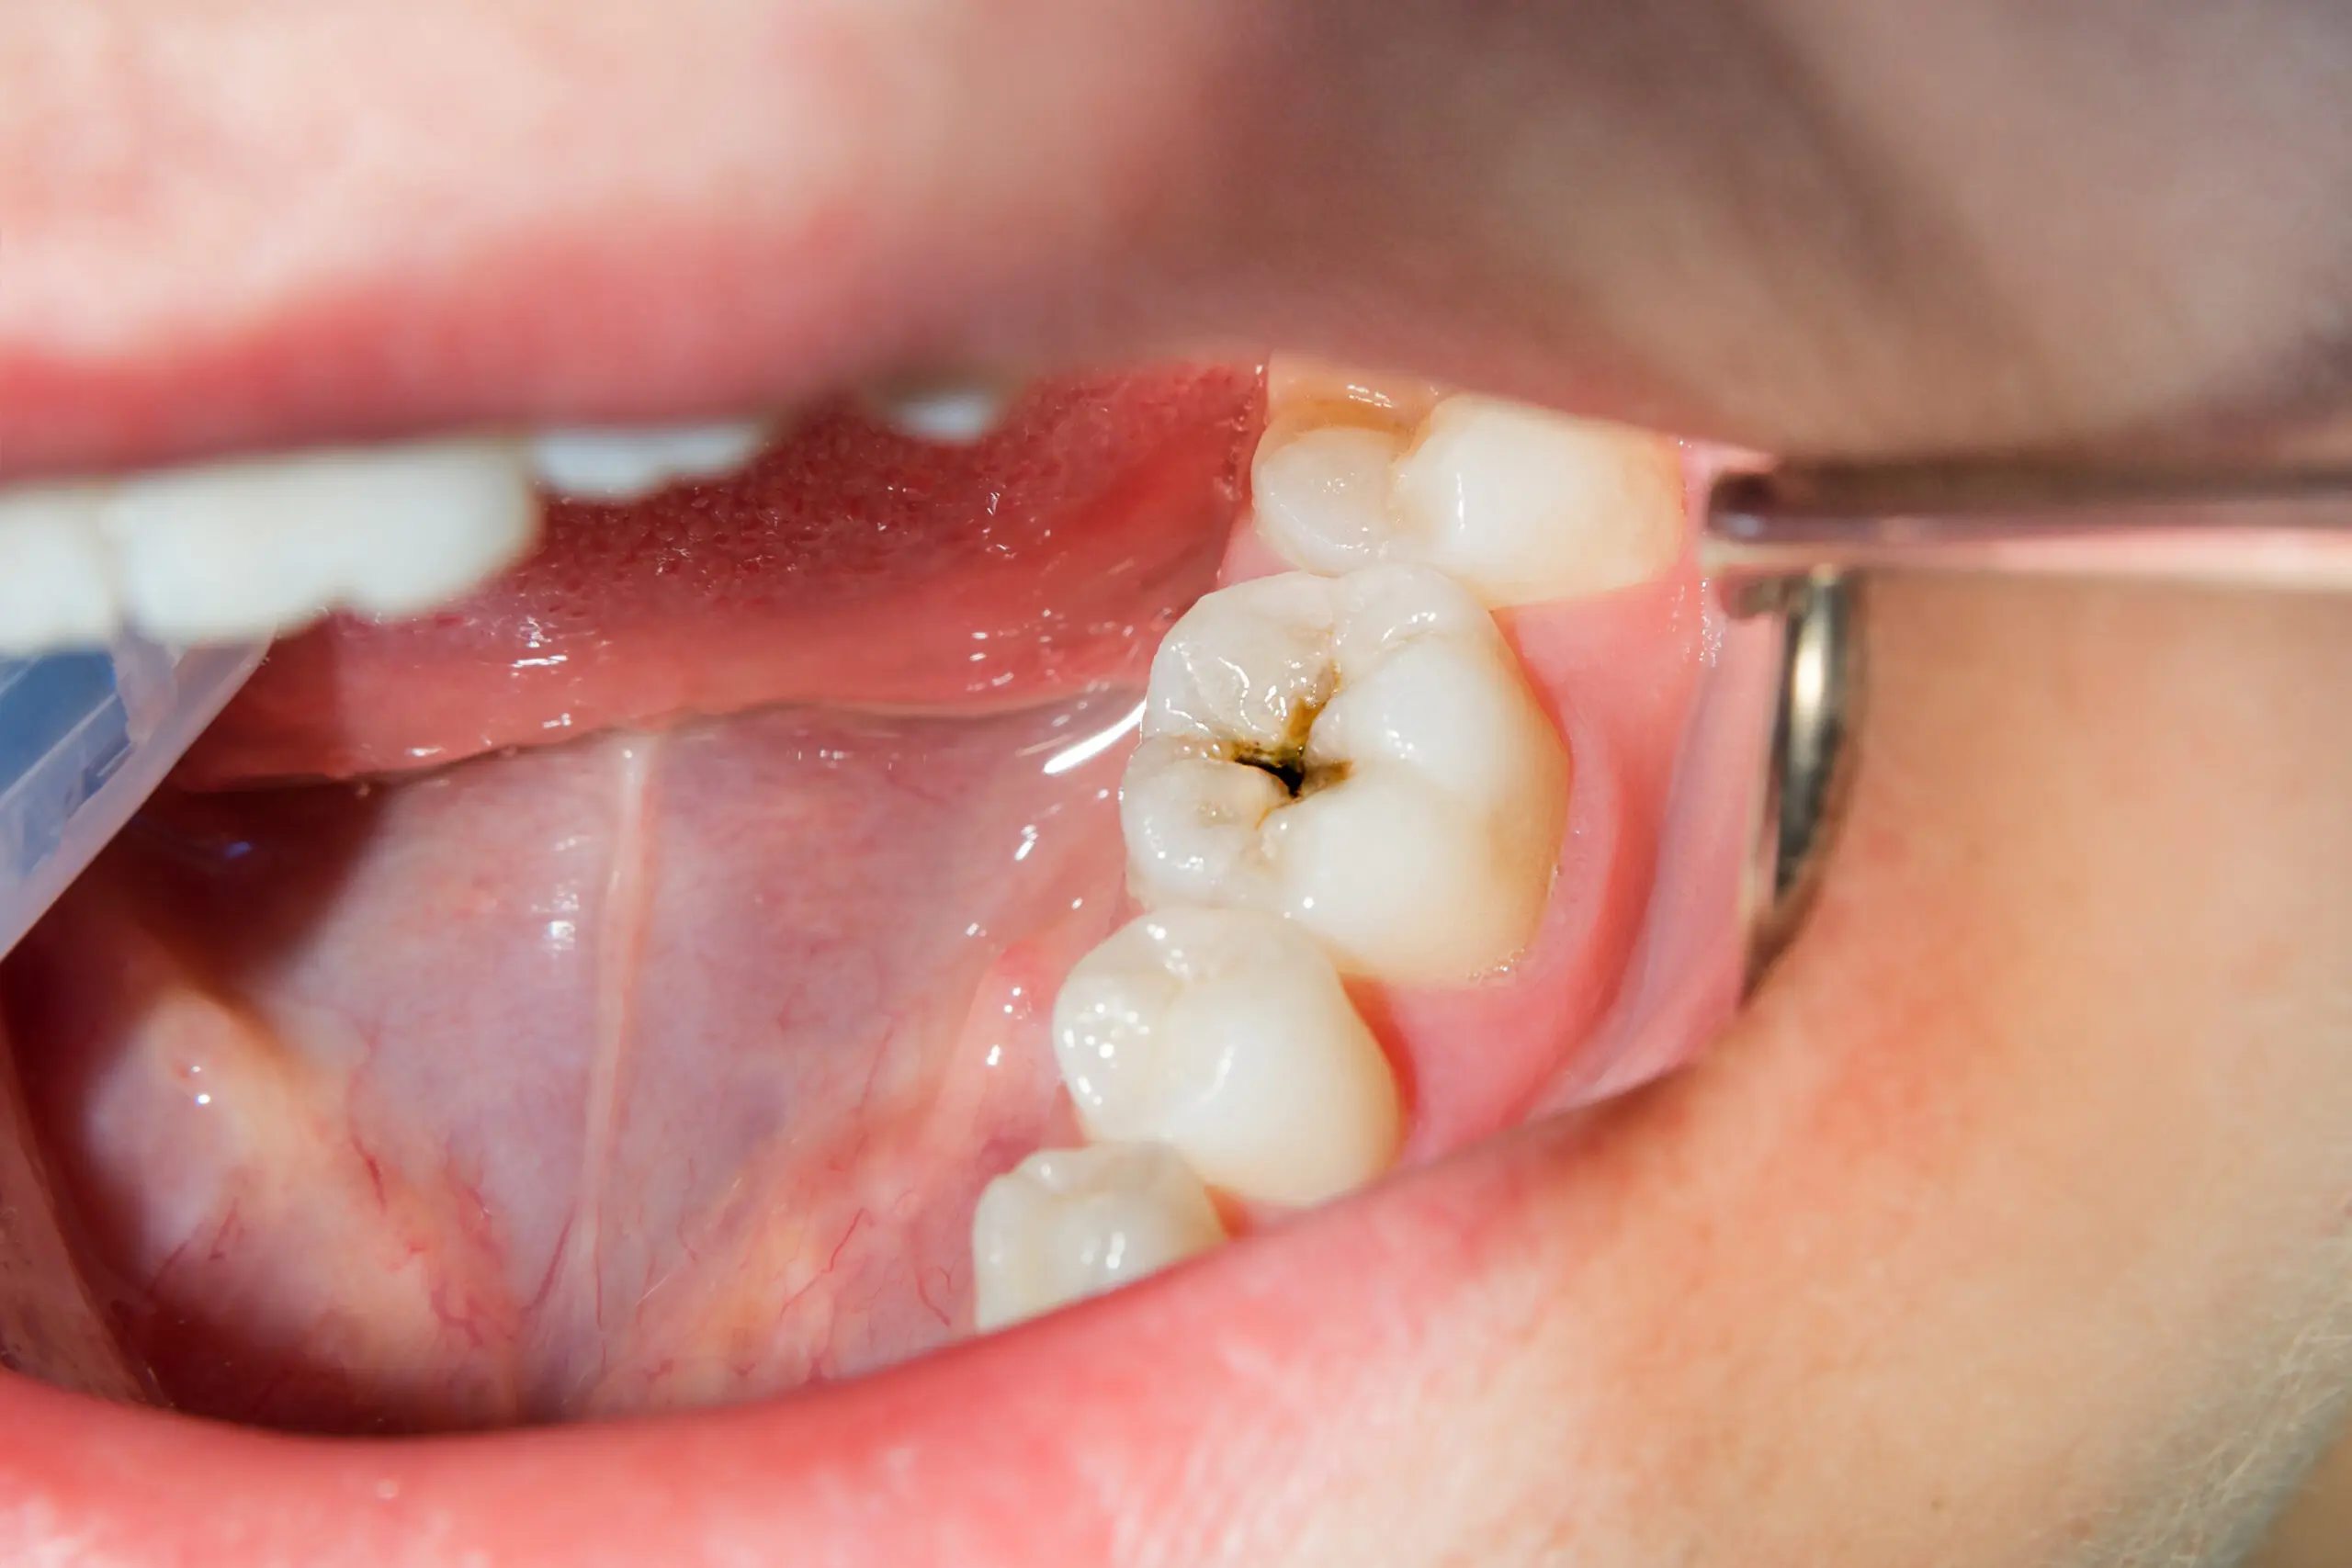

- Tercera fase: caries en la dentina

🔹 Qué sucede: La caries atraviesa el esmalte y llega a la dentina, una capa más blanda del diente.

🔹 Síntomas: Mayor sensibilidad y posibilidad de dolor leve o moderado.

🔹 Qué hacer: En esta etapa, la caries debe ser eliminada por un dentista y restaurada con un empaste o incrustación.